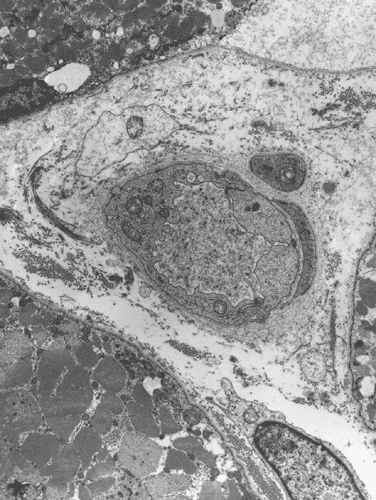

A biopsy was performed. The followings are representative photomicrographs of the biopsy material.

Pathology of the case:

| A. | B. |